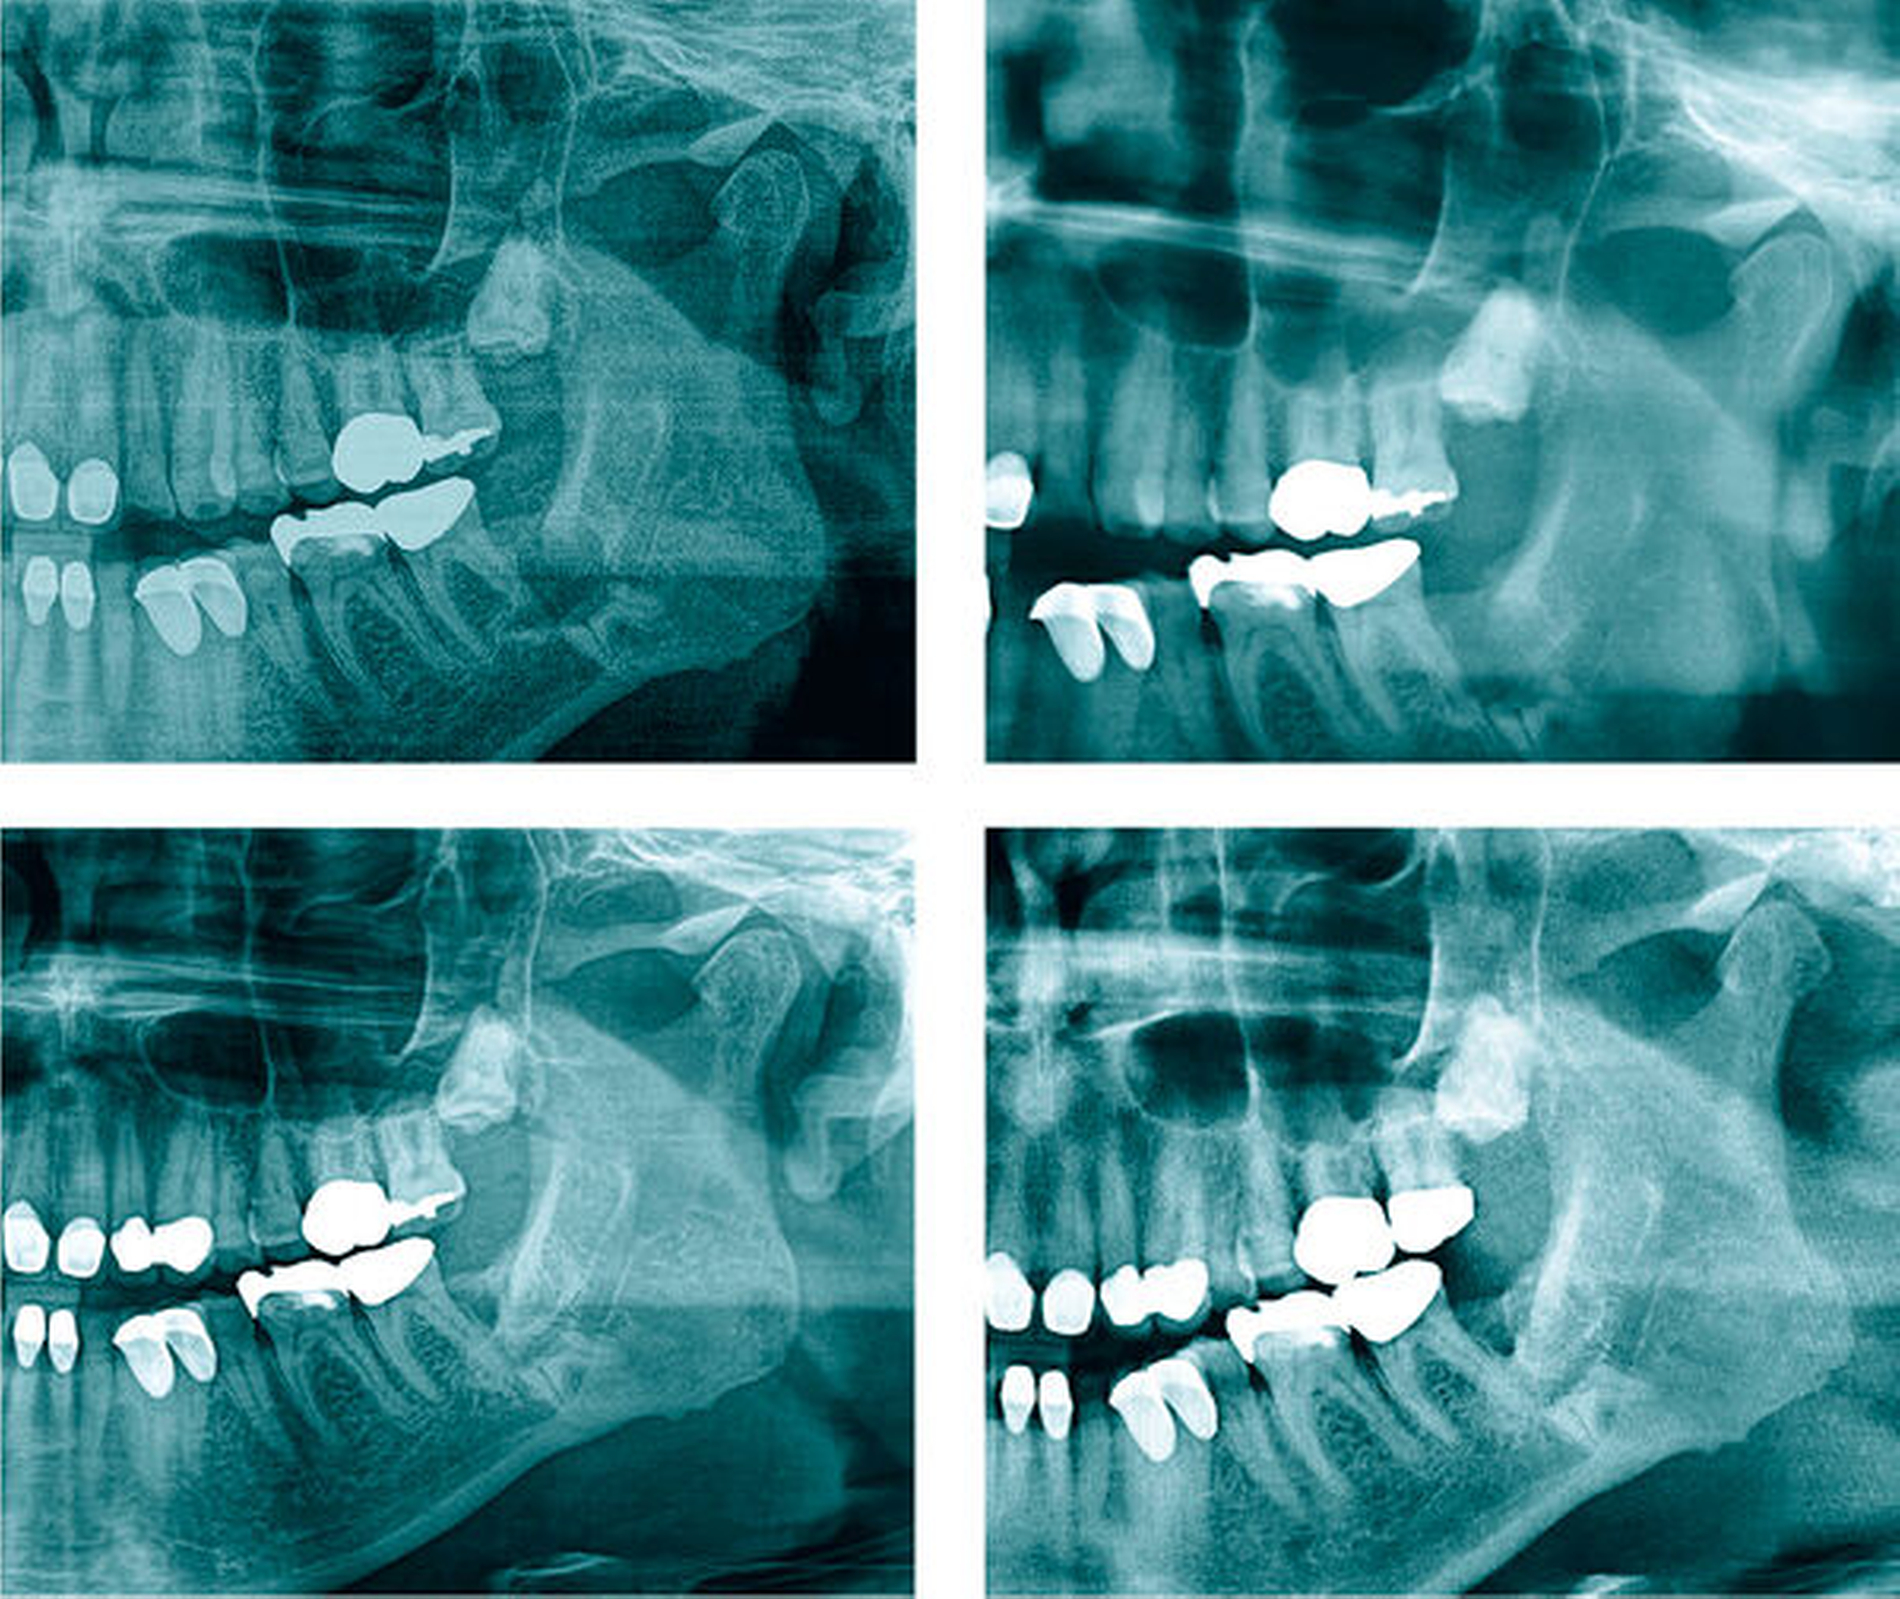

Die Patientin stellte sich eine Woche postoperativ zur röntgenologischen und klinischen Verlaufskontrolle erneut vor. Die Schmerzen und die Schwellung waren rückläufig, die Wunden enoral heilten regelrecht und unauffällig. Im Versorgungsgebiet des N. alveolaris inferior links war eine dezente Hypästhesie zu beobachten. Eine postoperative Panoramaschichtaufnahme (Abbildung 6) zeigte eine suffiziente Koronektomie rechts ohne verbliebene Schmelzanteile sowie leere Alveolen in Regio 38 und 28. Bei der anschließenden Untersuchung nach einer weiteren Woche zeigte sich die Patientin nahezu schmerzfrei, die Hypästhesie links war rückläufig.

Nach Abwägung der Risiken (Schädigung des N. alveolaris inferior, hoher Knochensubstanzverlust im Unterkiefer) war damals gemeinsam mit dem Patienten entschieden worden, eine Koronektomie am Zahn 38 durchzuführen. Die erste Verlaufskontrolle erfolgte im März 2015, bei der in der Panoramaschichtaufnahme eine Reossifikation nachgewiesen werden konnte (Abbildung 8). 2017 konnte röntgenologisch koronar der Radices 38 eine suffiziente Knochenneubildung festgestellt werden (Abbildung 8). Der Patient war beschwerdefrei, die Wundverhältnisse waren vollkommen reizlos und ohne Schwellung.

Aktuell wird bei ihm die operative Entfernung des Zahnes 28 geplant, der nun symptomatisch ist. Die Verlaufskontrolle nach der Koronektomie am Zahn 38 vor sieben Jahren zeigte auf der zur Planung der Entfernung von 28 angefertigten Aufnahme einen unauffälligen Befund mit deutlichem Nachweis einer Reossifikation im ehemaligen Kronenbereich (Abbildung 9). Der Patient gab an, dass er mit der Entscheidung damals zufrieden sei und er keinerlei Beschwerden in dieser Region habe.